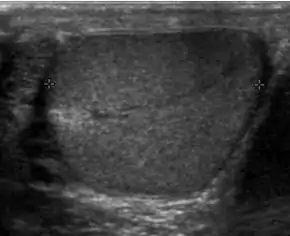

Fig. 26. Testicular torsion of the right testis. Absence of vascular flow and ill-defined hypoechoic lesions are seen in the testis.

The normal testis and epididymis are anchored to the scrotal wall. If there is a lack of development of these attachments, the testis is free to twist on its vascular pedicle. This will result in torsion of the spermatic cord and interruption of testicular blood flow. Testicular torsion occurs most commonly at 12 to 18 years but can occur at any age. Torsion results in swelling and edema of the testis, and as the edema increases, testicular perfusion is further altered. The extent of testicular ischemia depends on the degree of torsion, which ranges from 180° to 720° or greater. The testicular salvage rate depends on the degree of torsion and the duration of ischemia. A nearly 100% salvage rate exists within the first 6 hours after the onset of symptoms; a 70% rate, within 6–12 hours; and a 20% rate, within 12–24 hours. Therefore, testicular torsion is a surgical emergency and the role of ultrasound is to differentiate it from epididymitis as both disease presents with acute testicular pain clinically.

There are two types of testicular torsion: extravaginal and intravaginal. Extravaginal torsion occurs exclusively in newborns. Ultrasound findings include an enlarged heterogeneous testis, ipsilateral hydrocele, thickened scrotal wall and absence of vascular flow in the testis and spermatic cord. The ultrasound findings of intravaginal torsion vary with the duration and the degree of rotation of the spermatic cord. Gray scale ultrasound may appear normal if the torsion is just occurred. At 4–6 hours after onset of torsion, enlarged testis with decreased echogenicity is seen. At 24 hours after onset, the testis appears heterogeneous due to vascular congestion, hemorrhage and infarction. As gray scale ultrasound is often normal during early onset of torsion, Doppler sonography is considered as essential in early diagnosis of testicular torsion. The absence of testicular flow at color and power Doppler ultrasound is considered diagnostic of ischemia, provided that the scanner is set for detection of slow flow, the sampling box is small and the scanner is adjusted for the lowest repetition frequency and the lowest possible threshold setting.